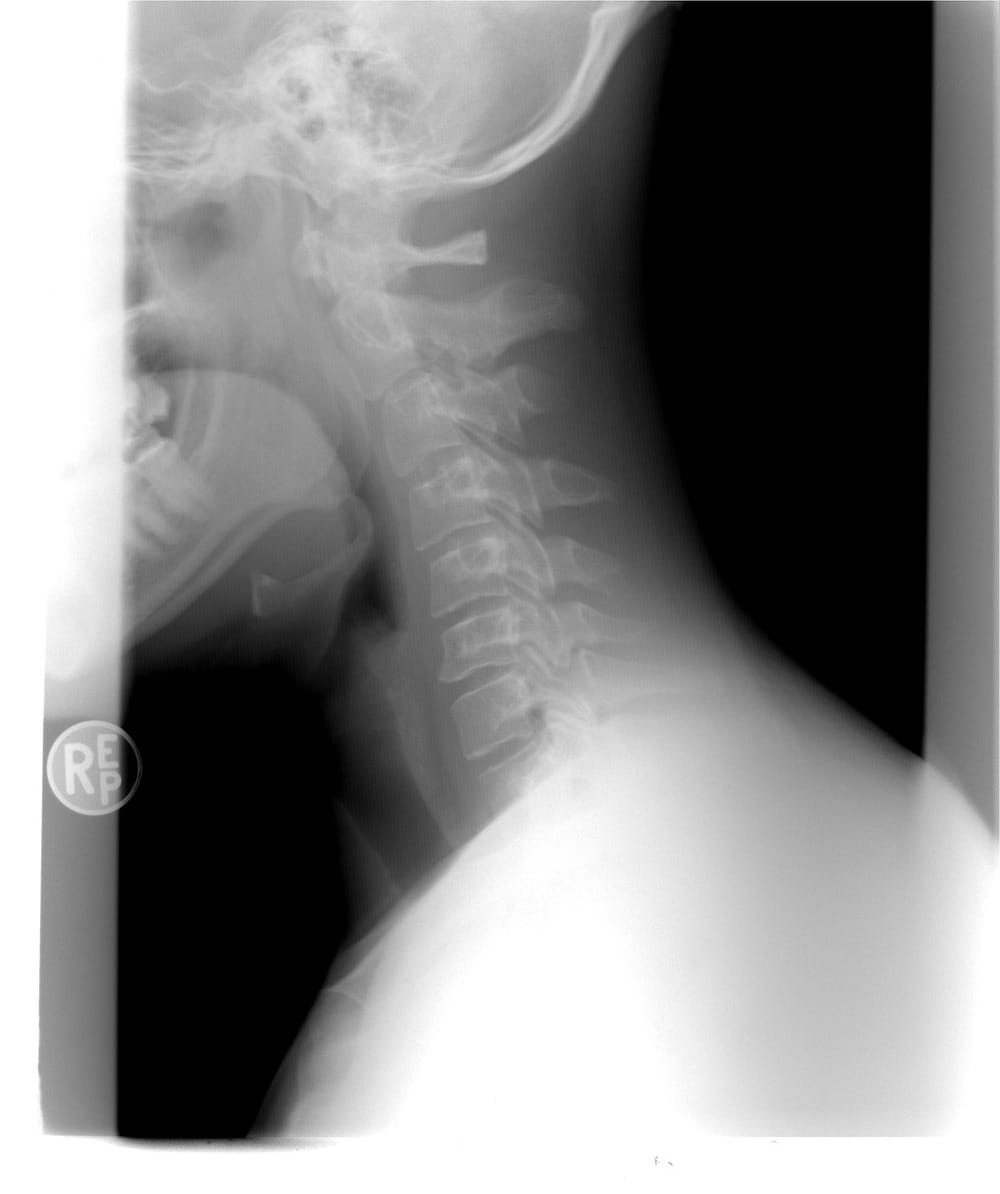

3 | Key Protein for Spinal Cord Repair Found

Zebrafish are amazing when it comes to regeneration. Even when their spinal cord is completely severed, it can completely restore itself. In humans, a severed spinal cord can leave them completely paralysed or dead. Research into spinal cord studies and stem cells have given many hope that one day broken spines can be fixed, and now we seem to be one step closer. By studying these tiny transparent animals, scientists have been able to pinpoint the exact protein that is responsible for re-joining the spinal cord and enabling it to work again. The protein in question is called CTGF, which stands for connective tissue growth factor. Humans also have CTGF, and although it differs slightly to the form found in zebrafish, when the human protein was added it worked in the same way. Although the protein is not the whole story, it gives scientists a clue to how regeneration works. The question now is what does the zebrafish have, that we humans don’t?

According to those working on the project, the next step is looking at regeneration proteins in mice.